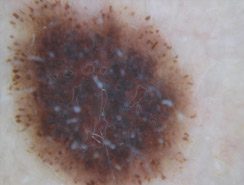

Dermatoscopia

Lo studio e la diagnosi delle neoformazioni cutanee attraverso strumenti specifici indicati per un'analisi delle caratteristiche strutturali superficiali e profonde delle varie neoformazioni cutanee: dermatoscopia, dermalite a luci fotocromatiche, mappatura nevica con videodermatoscopia digitale.

Al fine di una corretta diagnosi dei nevi, e dunque di un'efficace prevenzione da forme tumorali, è indispensabile visionare in profondità i caratteri di ogni formazione nevica. Ciò è reso possibile dall'utilizzo del dermatoscopio e dalla concomitante mappatura nevica, con l' eventuale rimozione chirurgica o laser di: